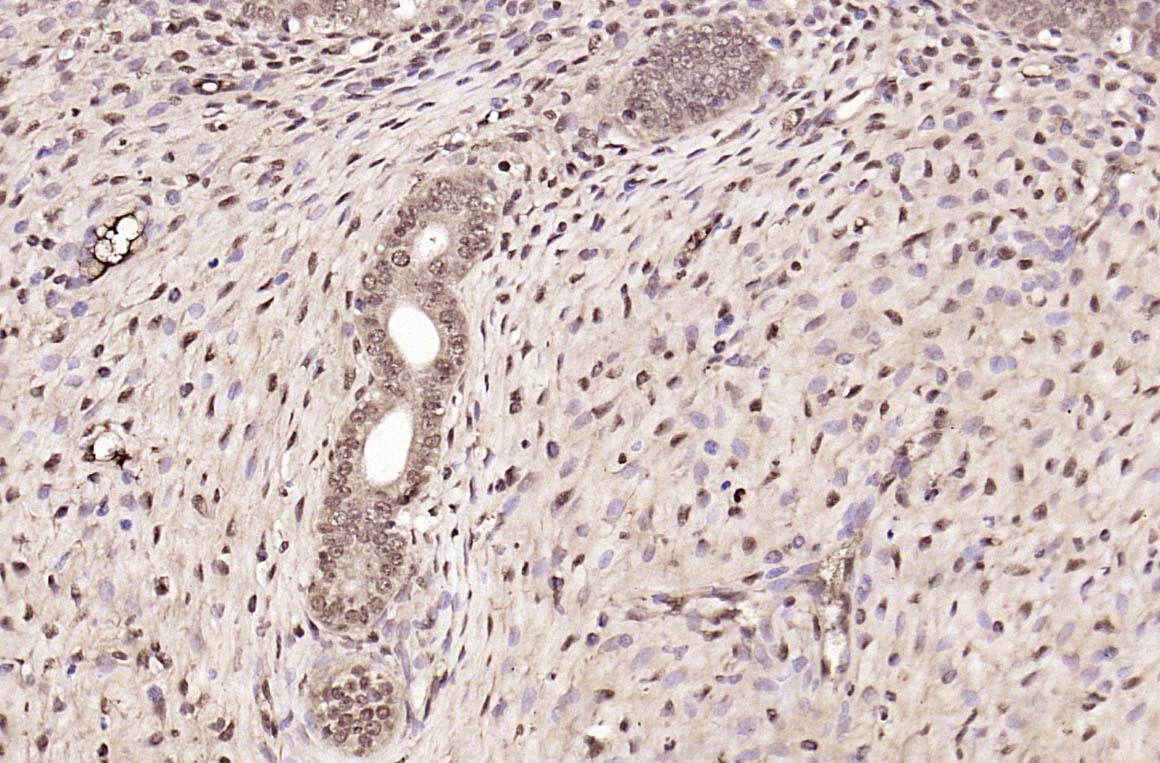

| 产品应用 | IHC-P=1:100-500, IHC-F=1:100-500, ICC/IF=1:100-500, IF=1:100-500, Flow-Cyt=2ug/Test Not yet tested in other applications. |

| {IHC-P} | {1:100-500} |